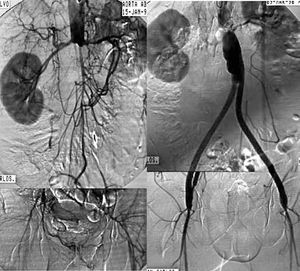

Revascularization surgery. Diffuse, extensive involvement is usually best treated by placement of an aortic-unifemoral or -bifemoral prosthesis (Figures 5 and 6). The effects of this well-systematized technique are known. The results in terms of permeability are above 85% and 80% at 5 and 10 years, with operative mortality below 5%.4 However, the technique involves major arterial surgery and requires quantifying the surgical risk to select the most suitable candidates. The operation in patients at high risk or who have a hostile abdomen (multiple reoperations, prior radiotherapy, active infection, etc) is carried out by means of what is referred to as "extraanatomic techniques," which enable revascularization of the limbs via non-anatomic pathways, and with less aggression. The most commonly used are axilo-unifemoral or -bifemoral, and femorofemoral bypass surgery. Both types of bypass surgery are performed via a subcutaneous tunnel, the former via the lateral region of the thorax and the abdomen, and the latter via the suprapubic region. They can be done with locoregional anesthesia. The figures for permeability with extraanatomic bypass surgery are lower, ranging between 40% and 70% at 5 years, depending on the clinical indication.4 They are, therefore, rarely indicated in the absence of critical ischemia.

Figure 5. Arteriography showing extensive aortoiliac occlusion and the result after aortobifemoral bypass surgery.